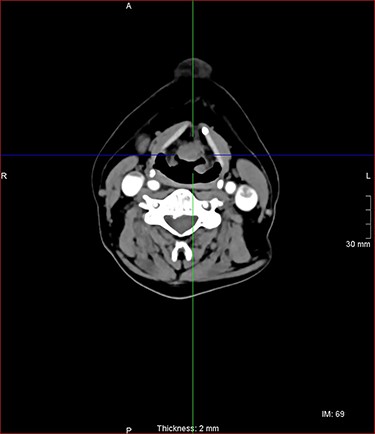

A laryngeal abnormality was noted, and he was referred to ENT for further assessment (Fig. 1). Flexible nasendoscopy showed a lesion on the laryngeal surface of the epiglottis in the midline. Vocal cords were not affected, although the lesion was extending close to the anterior commissure. An 18 × 14-mm lesion was found on magnetic resonance imaging (MRI) at the right paracentral supraglottic region, crossing the midline with possible involvement of the base of epiglottis (Fig. 2). There was no destruction of the thyroid cartilage or hyoid bone, and no involvement of the para-epiglottic space or glottis. There were no pathological cervical lymph nodes. Further CT scanning of the neck and chest confirmed the above, with no lung metastases identified (Figs 3 and 4).

sagittal postcontrast CT images of the neck with similar lesion related to the base of epiglottis, no involvement of the pre epiglottic fat.